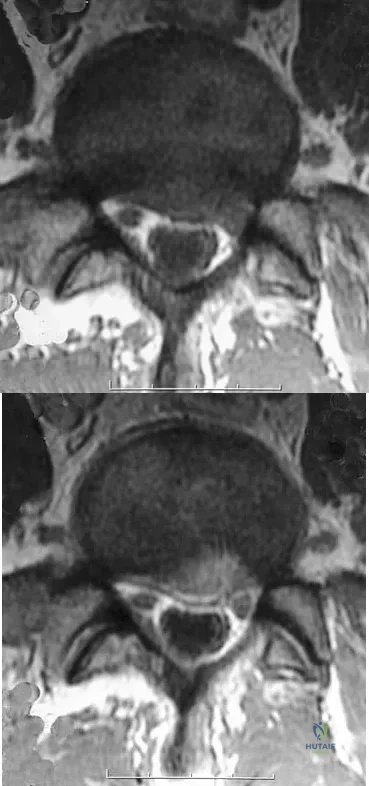

A patient who underwent an L5-S1 diskectomy 18 months ago has persistent pain in the left leg. Figures 9a and 9b show postoperative axial T1-weighted MRI scans at the L5-S1 level without and with gadolinium. What is the most likely diagnosis?

Explanation

Persistent or recurrent symptoms after lumbar diskectomy are troublesome and can be difficult to assess. Gadolinium-enhanced MRI scans may be helpful. The images show enhancement about the left S1 root, a finding that is most consistent with perineural (epidural) fibrosis. The root itself does not enhance. Root enhancement has been associated with compressive radicular symptoms. A disk herniation does not enhance with gadolinium. A neurilemmoma enhances with gadolinium, but the involved root would be enlarged. There is no evidence of a fluid collection which would be consistent with an epidural abscess. Babar S, Saifuddin A: MRI of the post-discectomy lumbar spine. Clin Radiol 2002;57:969-981. Kikkawa I, Sugimoto H, Saita K, et al: The role of Gd-enhanced three-dimensional MRI fast low-angle shot (FLASH) in the evaluation of symptomatic lumbosacral nerve roots. J Orthop Sci 2001;6:101-109.